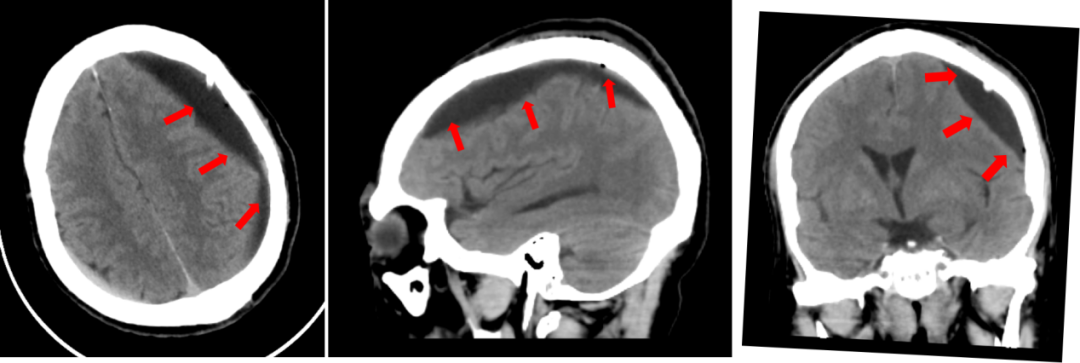

术后CT

术后患者转至发热门诊楼隔离病房,复查CT结果显示颅内血肿清除干净,患者精神状态也同步好转。“感谢你们这么快速地反应,及时给我父亲手术!”患者家属激动地说。“如果发生脑外伤,即便当下没事,也要警惕迟发颅内出血风险,也就是咱们医学上说的慢性硬膜下出血。”张培海提醒道。慢性硬膜下血肿一般出现在外伤后三周到三个月之间,特别是60岁以上老年人群、长期口服阿司匹林的抗凝人群需要注意。